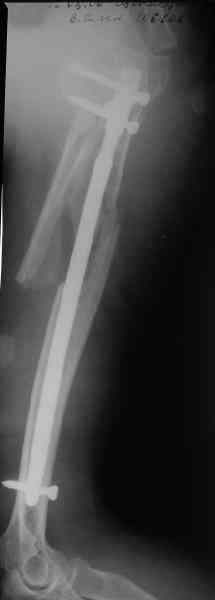

Здесь нет необходимости в серкляже. Вмешиваться на промежуточных отломках приходится, если есть угроза перфорации кожи, или промежуточный отломок попал в фасцию, как пуговица в петлю. В приложении сегментарный оскольчатый перелом плеча в проксимальном отделе, фиксированный больщеберцовым стержнем. Как видите, обошлось без серкляжа. Функция полная.

Александр, великолепные снимки! Вопрос - что за гвоздь?

Это укороченный большеберцовый стержень, которые делает предприятие "ЦИТО".

на синтезовский UTN похож))

Скажите пожалуйста, Александр Николаевич, почему Вы использовали большеберцовый гвоздь?

Доступные на тот момент гвозди для плеча имели худшие возможности фиксации в коротком проксимальном отломке.

Уважаемый Александр Николаевич! На продемонстрированных вами рентгенограммах имеется достаточно большое на мой взгляд смещение отломков после фиксации блокируемым гвоздем. На счет полной функции все понятно, а нет ли каких либо сосудистых расстройств конечности? Имею ввиду венозную недостаточность или лимфостаз.